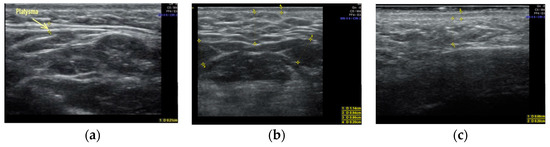

Clinical case #4. During the study, a 51-year-old male patient with a 9 MHz linear transducer of soft tissues of the lower third of the face and neck without pressure, in an upright position, showed denser platysma (diameter 2.1 mm) without signs of involutive changes (Figure 4a), and also displayed excessive accumulation of adipose tissue in the chin (Figure 4b) and along the contour of the lower jaw (Figure 4c).

B-mode ultrasound examination of the soft tissues of the lower face and neck area with a 9 MHz linear transducer. Platysma (a), excessive accumulation of adipose tissue in the submandibular area (b), and along the contour of the lower jaw (c).

According to the results of the ultrasound examination, this was only enough to influence the fatty tissue in the submental area and along the contour of the lower jaw to obtain younger contours of the lower face and neck in this clinical observation.

When comparing the results of the ultrasound examination of the soft tissues of the lower third of the face and neck in male (n = 14) and female (n = 73) patients, we noted that in males, involutive changes in platysma were observed at an older age than in women. It was noted that the platysma muscle itself in males (1.7 ± 0.3 mm) was thicker (0.35 ± 0.8 mm (±SE standard deviation average)) than in females, and denser (Figure 4 and Figure 5), which has a beneficial effect on its tone and prevents early ptosis of these tissues.